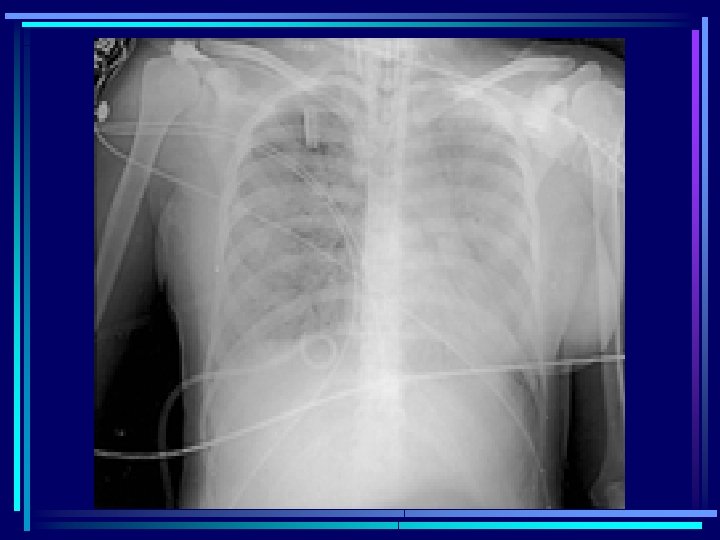

Clínica ü Periodo de isquemia-hipoxia y reperfusión ü SDMO: § Cardiovascular (arritmias, disfunción miocárdica, shock) § Respiratorio: LAP -> SDRA § Neurológico: hasta muerte encefálica § Renal: hasta en el 50 % § Coagulación: hemolísis y CID

Tratamiento en el hospital ü Mantener o iniciar las maniobras de RCP avanzada ü UCI ü Valoración clínica, Rx (columna), bioquímica. . . ü Evaluar posibles lesiones asociadas ü Tratamiento de la hipotermia ü Resucitación cerebral avanzada ü ¿ antibióticos, esteroides ?